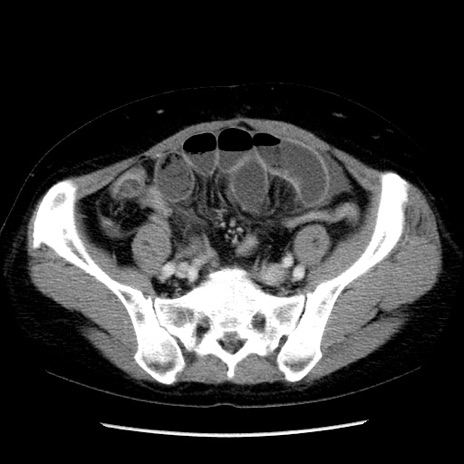

症例6(横断像)

【症例】50歳代女性

【主訴】下腹部痛

【現病歴】本日朝より下痢2回あり。 昼食を食べた後、嘔吐3回、下腹部痛認め、症状軽快せず、当院救急搬送。

最終食事:本日昼(生ものなし)。 昨日の夜、刺身を食ぺたとのこと。周囲に同様の症状の者なし。普段、排便は毎日あるとのこと。

【既往歴】卵巣癌術後(8年前に当院で卵巣摘出)

【身体所見】 意識清明、腹部:平坦、腸蠕動音→、やや硬、下腹部自発痛・圧痛あり、反跳痛あり、筋性防御なし。

【データ】WBC 16000、CRP 0.01